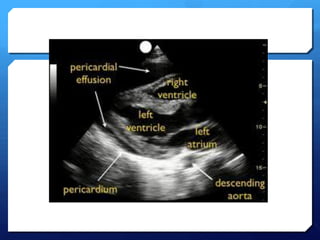

PericardialTamponade

 Remember tamponadeis a clinical diagnosis based on

patient’s haemodynamics and clinical picture.

 Ultrasound may demonstrate early warning signs of

tamponade before the patient becomes haemodynamically

unstable.

 Haemodynamic effects

 Its PRESSURE NOT SIZE THAT COUNTS!

 Rate of formation affects pressure-volume relationship and

is therefore more important than volume of fluid.

Tamponade using ultrasound

 A moderate-large effusion.

 Right atrial collapse

 Atrial contractionnormal in atrial systole

 Collapse throughout diastole or inversion is abnormal.

 RV collapse during diastole when meant to be filling

(‘scalloping’ seen)

 Whats seen in the IVC…